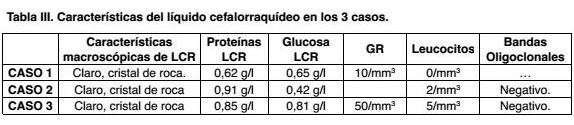

Tomografía (TAC) cráneo: sin evidencia de isquemia aguda. Mínima asimetría en surcos parietales izquierdos. Estudio del LCR: líquido normotenso, cristal de roca, proteínas: 0,62 g/L, glucosa: 0,65 g/L, glóbulos rojos 10/mm3, glóbulos blancos 0. Bacteriológico y reacción en cadena de la polimerasa (PCR) para virus negativo. EEG: actividad de fondo con ondas lentas, superpuesta con ondas rápidas sin actividad epileptógena.

En emergencia paciente vigil, limitación en la flexión de nuca, sin alteraciones de pares craneanos o espinales. TAC cráneo normal. Estudio del LCR: cristal de roca, glóbulos blancos 2 mm3, proteínas 0,91 g/L, glucosa 0,42 g/L. PCR para herpes y enterovirus, tinta china, antígeno neumocóccico, directo y cultivo negativos.

Estudio del LCR: aspecto líquido claro, ligeramente turbio sin coágulos, escaso sedimento hemático. Leucocitosis 5/mm3, GR 500/mm3, Proteína 0,91 g/L, Glucosa 0,81 g/L. PCR para Herpes 1, 2, 6, CMV, Epstein Barr, Varicela Zóster: negativos.

Recientemente, se proponen nuevos criterios en base a los grados de certeza del diagnóstico(3). Estableciendo el diagnóstico definitivo con histología positiva y diagnóstico probable en ausencia de ella, pero con hallazgos en la angiografía, RM y alteraciones en el LCR asociados con un cuadro clínico compatible con VPSNC (Tabla I). Varios estudios han reportado una sensibilidad de la RM para VPSNC cerca de 100%(1,11). En nuestros pacientes todos presentaron alteraciones inespecíficas y variables en la misma, como el compromiso de múltiples estructuras encefálicas en diferentes territorios vasculares, lesiones hiperintensas en T2 y FLAIR, con realce con el contraste a nivel de leptomeninges como se ve en los Casos 1 y 3. Las alteraciones en el LCR, un hecho casi constante en estos pacientes se caracterizan por la presencia de hiperproteinorraquia evidenciada en los tres casos, no presentando alteración del recuento celular ni en los niveles de glucosa (Tablas II y III).